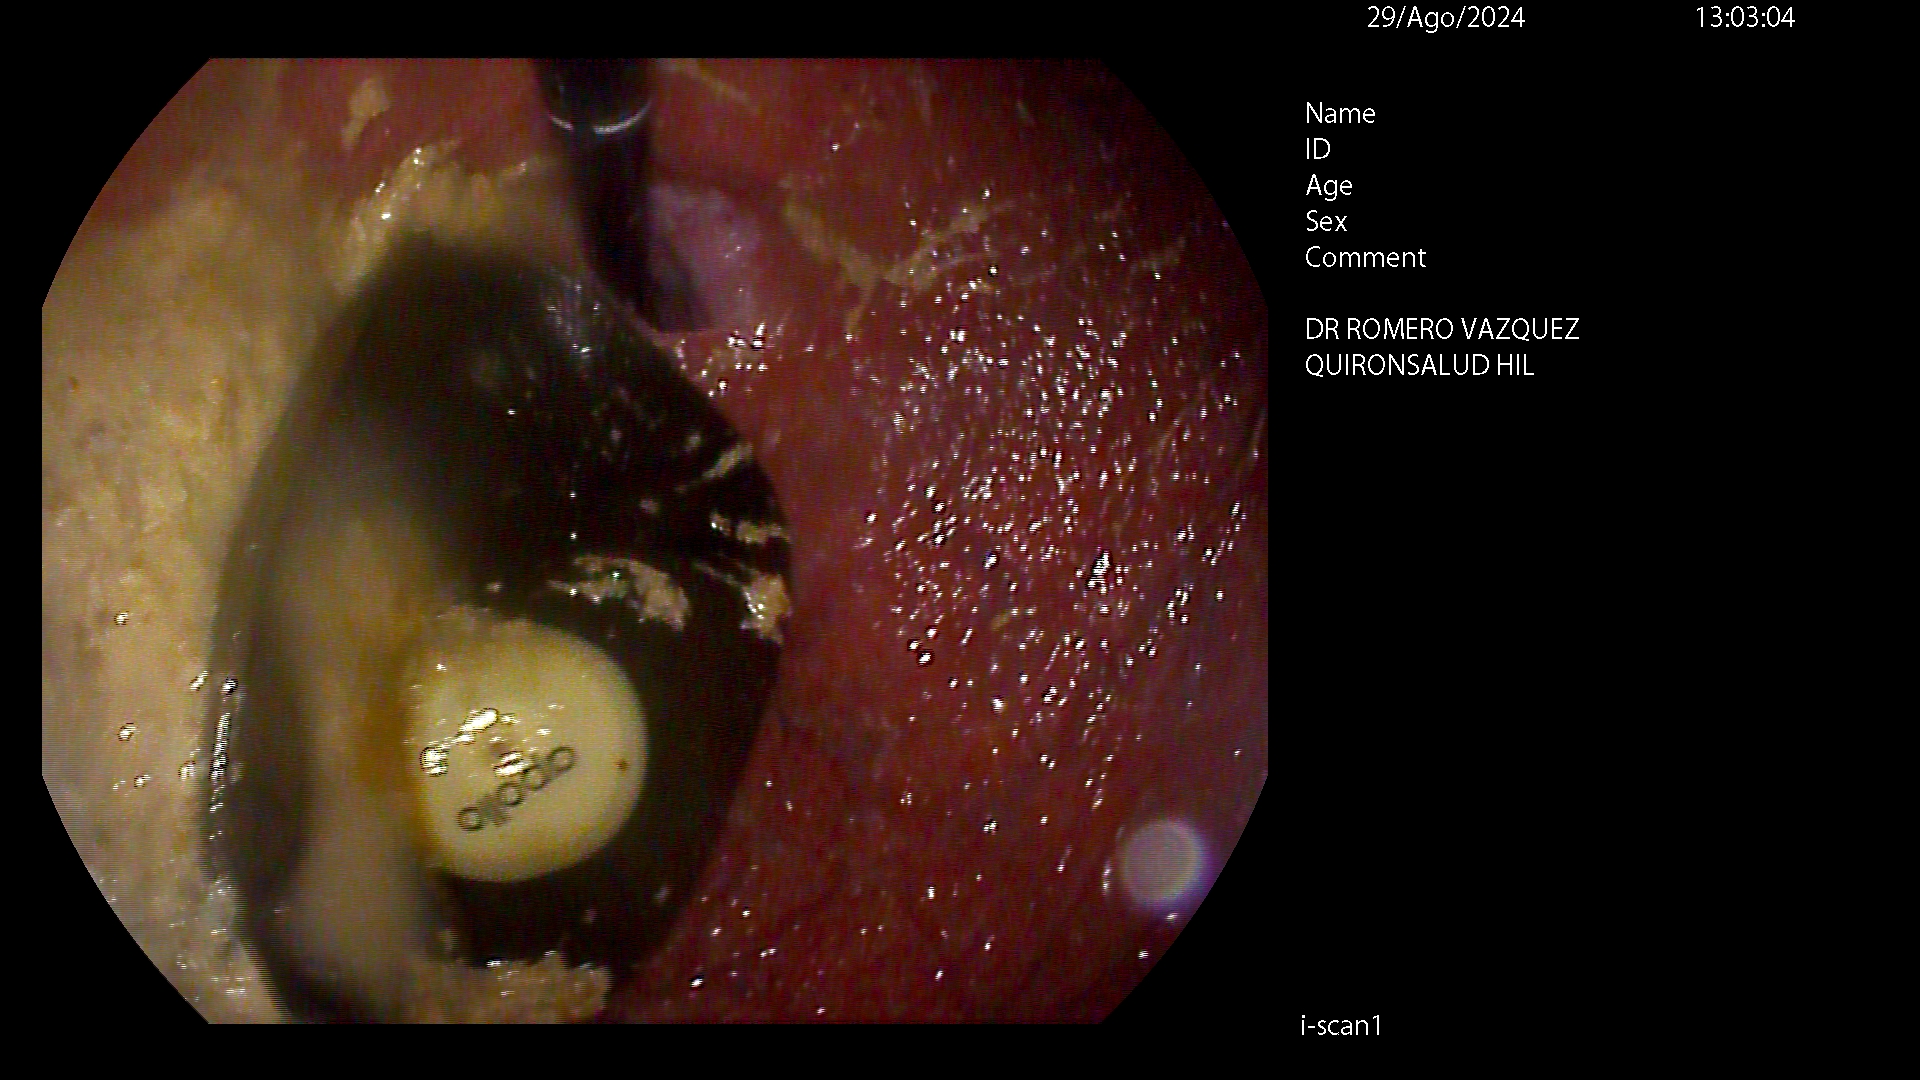

APOLLO

Comúnmente conocido como “manga gástrica endoscópica” o “manga gástrica sin cirugía”, el método Apollo es una técnica endoscópica mínimamente invasiva que permite reducir el estómago entre un 60 y un 80% de su tamaño inicial, sin realización de incisiones externas y, por tanto, sin cicatrices. Está indicada para pacientes con un IMC entre 30 y 40, o para pacientes con un IMC superior a 40 que no desean enfrentarse a técnicas quirúrgicas para reducción de peso de mayor envergadura y por ende, de mayor riesgo.

Mediante un sistema de sutura acoplado a un endoscopio, se sutura el estómago “desde dentro” dándole un aspecto similar al conseguido por la cirugía de gastrectomía vertical laparoscópica (manga gástrica quirúrgica), pero con menor riesgo quirúrgico y muy buenos resultados a medio y largo plazo. De esta manera se limita la cantidad de comida que puede entrar en el estómago e igualmente hace que la digestión sea más lenta, favoreciendo enormemente la saciedad y la pérdida de peso. Es una técnica definitiva, pero por vía oral, ni realizar heridas abdominales ni cicatrices.